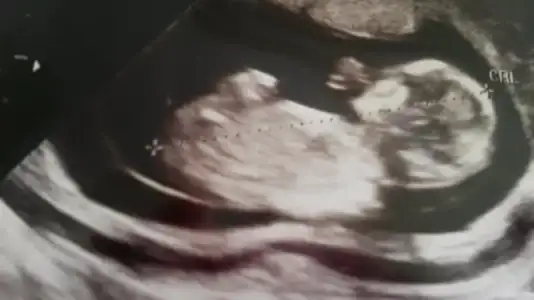

Eki Görüntüle 473829 bu bir erkek bebek genital nub cikintisi gayet yukarda

Eki Görüntüle 473831 simdi burada cikintilara bakin eger bel popo cizgisine paralel ise kiz

yok 30 derecelik bir aciyla yukari bakiyorsa erkek